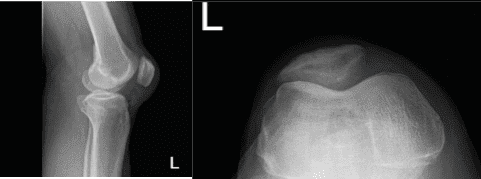

Un hombre de 50 años con molestias de dolor en la rodilla izquierda visitó nuestra consulta. Recuerda una lesión en una caída, que no puede presionar la rodilla. También dice que siente un espacio entre la rótula.

Fue examinado físicamente y se le realizó una resonancia magnética, que mostró una ruptura completa del cuádriceps junto con una rotura lateral del menisco y una rotura parcial del LCA. El paciente acudió a urgencias por un dolor intratable. Hablamos sobre las opciones de tratamiento y el paciente optó por el manejo quirúrgico.

El paciente fue sometido a una cirugía artroscópica. Los procedimientos realizados incluyeron meniscectomía lateral parcial, condroplastia, desbridamiento del LCA y reparación abierta del cuádriceps de la rodilla izquierda. Se creó un portal de entrada lateral izquierdo y se accedió al telescopio.